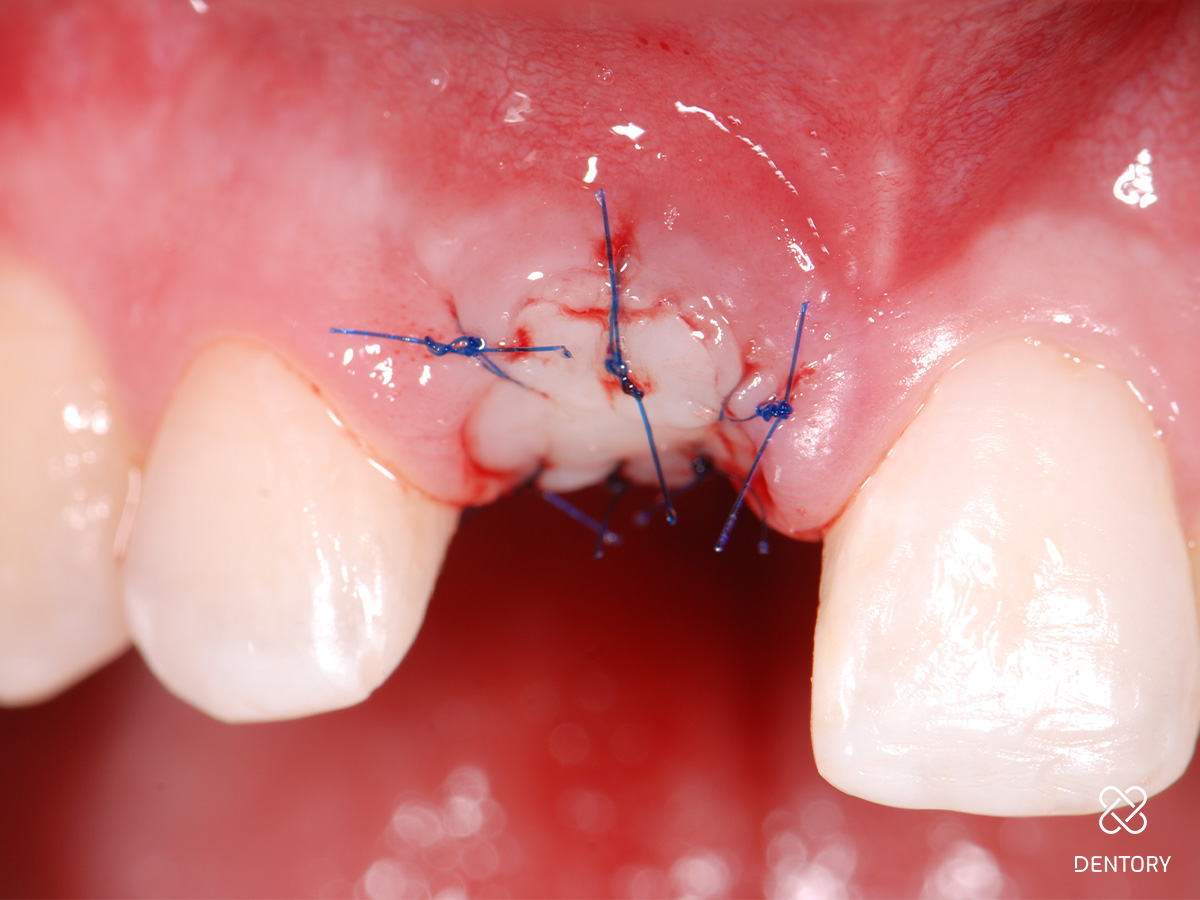

Abbildung 10

Eingenähter Punch vom seitlichen Gaumen: Die Entnahme kann im Prämolaren- oder Tuberbereich erfolgen.

Abbildung 11

Das Transplantat kann mit wenigen Mikronähten fixiert werden; die Passung sollte wie bei einem Korken mit etwas Druck sein.